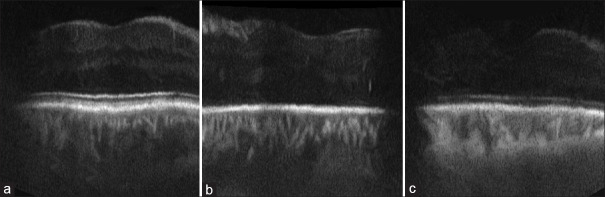

Methods: Much specifically, retinal AI-CADs have been developed to assist ophthalmologists in analyzing optical coherence tomography (OCT) images and making retinal diagnostics simpler and more accurate than before. Retinal AI-CAD technology could provide a new insight for the health care of humans who do not have access to a specialist doctor. AI-based classification methods are critical tools in developing improved retinal AI-CAD technology. The Isfahan AI-2023 challenge has organized a competition to provide objective formal evaluations of alternative tools in this area. In this study, we describe the challenge and those methods that had the most successful algorithms.

Results: A dataset of OCT images, acquired from normal subjects, patients with diabetic macular edema, and patients with other macular disorders, was provided in a documented format. The dataset, including the labeled training set and unlabeled test set, was made accessible to the participants. The aim of this challenge was to maximize the performance measures for the test labels. Researchers tested their algorithms and competed for the best classification results.